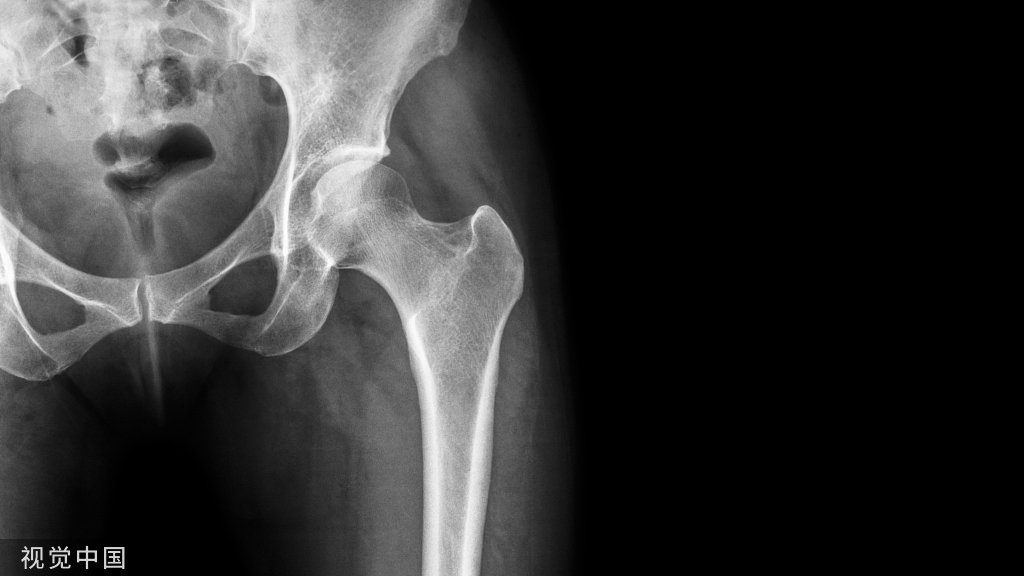

以Whiteside线确定股骨假体旋转程度,安放截骨导向板,外侧钉孔放于原先的位置,内侧钉孔抬高,使两钉孔连线与胫骨截骨面平行。

接下来,在截骨导向板的引导下,完成股骨的截骨。